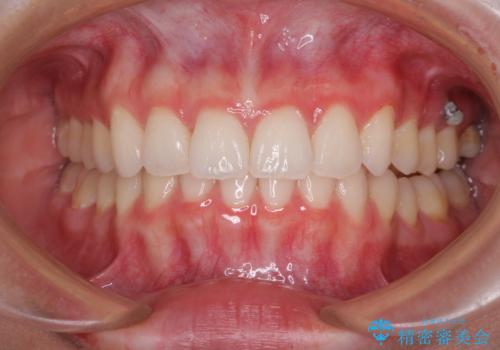

- 前歯2本が飛び出してることを気にして来院された患者様です。

全体的に黄ばんだ歯の色も気になるとのことで、マウスピース矯正により飛び出した前歯を治しつつ、ホームホワイトニングを併用して黄ばみを解消していくこととしました。

歯と歯の間を削ることで、飛び出した前歯が引っ込み、スッキリとした口元となりました。

歯の黄ばみも改善され、明るい歯並びとなりました。